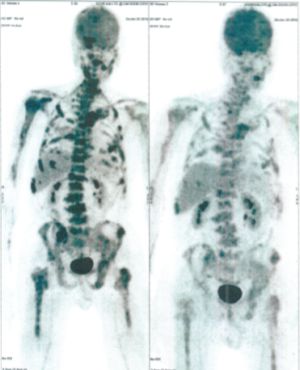

Below are some of the cases, from more than 80 cases we have treated so far with good results. When reading the PET/CT scans, the picture on the left is before treatment, and the picture on the right is after treatment. The intensity of black represents the activity of the cancer, but some black areas are not cancer: brain, heart, radioactive urine in bladder. For the heart, the intensity of black depends on the number of hours of fasting: if more than 10 hours, the heart is not even black, but if fasting is less than 6 hours, it is very black. The intensity of black in the brain can be variable in different scans depending on the brain activity at the time of the scan. The intensity of black in the radioactive urine can also be variable due to the hydration of patients and the time of injection of diuretic.

CASE NO: 1

(HEPATOCELLULAR CARCINOMA + STOMACH CANCER)

A middle-aged women who is very thin and very weak, can hardly walk, lying in bed most of the time. She saw a cancer specialist in a top hospital who discovered that she had massive hepatocellular carcinoma, and another cancer in the stomach. Given that hepatocellular carcinoma is incurable and stomach cancer is very difficult if not impossible to cure without surgery, she was told that nothing could be done for her. She came to ask us to help her. After just 4 treatment, the hepatocellular carcinoma went into remission, and the stomach cancer (arrow) became less active. Until today, more than 6 months later, the hepatocellular carcinoma is still in remission.